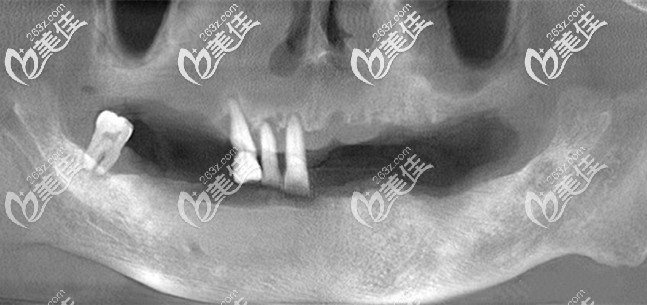

為我面診的是孫醫(yī)生,根據(jù)CT片的結(jié)果來看,牙槽骨吸收比較厲害,僅有的四顆牙齒已經(jīng)能看到牙根,建議拔除后直接做全口種植牙。

目前較為先進的種植技術(shù)則是即刻種植技術(shù),而我的骨量也符合做全口即刻種植牙,為了縮短治療時間,降低成本,醫(yī)生建議我選擇allon4/6全口種植牙。

由于我的骨量還算可以,所以選擇了更加穩(wěn)固的半口6顆種植牙,自然價格也要比半口4顆要貴呀,全口種植牙花了我14萬元,用的是常見的登騰(Dentium)種植體。